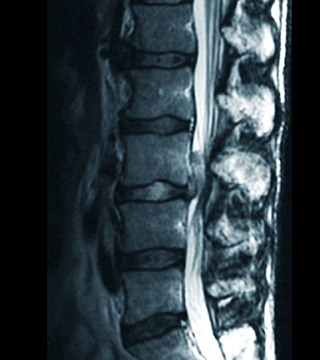

• 허리디스크

노화나 외부적인 자극으로 인해 디스크가 손상을 입으면서 섬유륜이 손상 혹은 파열되면서 디스크 내부의 수핵이 빠져 나와 지나가는 신경을 압박해 증상이 나타나는 질환입니다.

최근에는 2~30대에서도 많이 발생하는 국민 척추질환입니다.

허리디스크 치료방법

• 비수술적 치료 풍선확장술, 신경성형술, 경막외내시경시술(꼬리뼈내시경술)

• 수술적 치료 현미경디스크제거술, 내시경디스크제거술, 척추유합술

• 척추관협착증

흔히 50대에 가장 많이 발생하는 꼬부랑 노인병으로 알려져 있으며 허리디스크와 증상이 비슷합니다. 오랜 시간 뼈, 인대, 디스크 등이 퇴화되면서 척추관이 좁아져 발생하는 질환입니다.